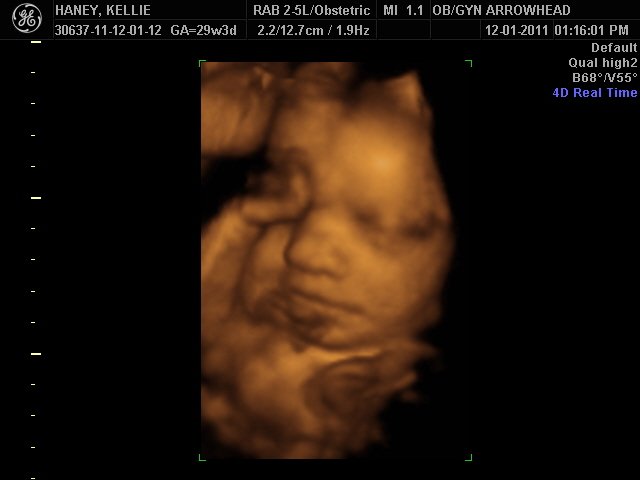

We offer complimentary 3D/4D Ultrasounds to all our OB patients around 30 weeks! The following photos are some examples of our work, shown with permission from our patients.